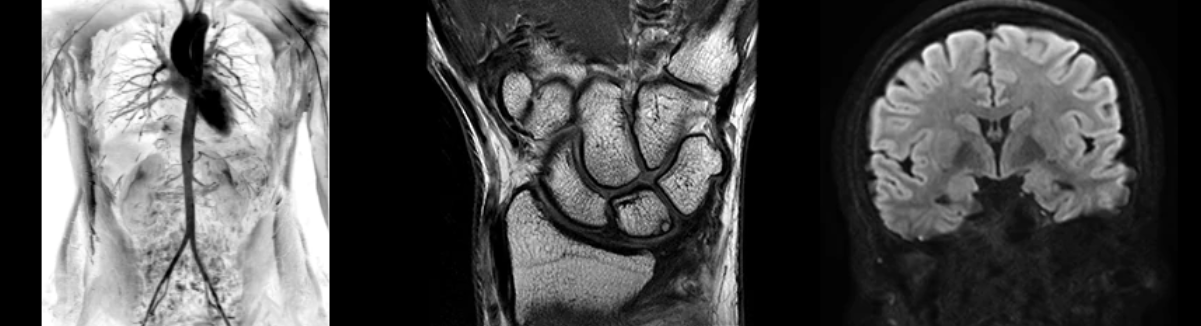

Представляет собой универсальное решение для визуализации анатомии головного мозга, позвоночника, сосудов и периферических нервов с четкой дифференциацией тканей.

Программное решение OrthoWorks разработано для визуализации структур опорно-двигательного аппарата с прекрасным контрастированием тканей.

Используйте BodyWorks для визуализации абдоминальной и тазовой областей с учетом любых типов пациентов.